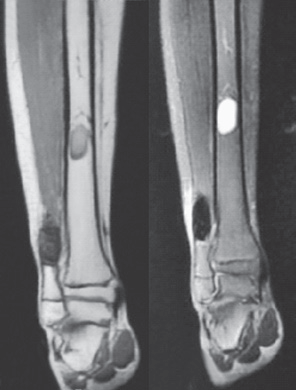

男,15岁,右踝部间断疼痛2年,加重伴右踝部肿胀1周。查体:右外踝上6cm处略肿胀,局部皮温正常,未触及包块,局部压痛明显,右踝关节活动度基本正常。右胫腓骨正侧位平片(图1):右腓骨远端干骺端膨胀性骨破坏,骨密度减低,骨皮质变薄,病灶内有分房,未见骨膜反应及周围软组织影。胫骨中下段髓腔内可见类圆形影,边界清楚,骨皮质无破坏。右踝MRI示:腓骨下段髓腔内显示4.5cm×2cm等T1、短T2异常信号灶,边界清楚,信号不均,其内可见分隔,病灶呈膨胀性生长,骨皮质变薄(图2)。右胫骨中下段髓腔内显示3.7cm×1.7cm椭圆形长T1、T2信号灶,边界清楚,信号均匀,边缘规则,骨皮质连续。结合病史及影像学表现考虑为良性病变,遂在硬膜外麻醉下行右腓骨远端病灶刮除、异体骨植骨、内固定术,右胫骨病灶刮除术。术后病理报告:(1)右腓骨远端髓腔内有5cm×4.5cm×1.3cm肿块。镜下见大片的梭形细胞伴有较多体积较大的多核巨细胞,局部见新生的骨小梁样结构,结合临床,考虑为GCT(图4)。(2)右胫骨远端髓腔内见灰黄色结节肿物,总体积3.5cm×3cm×1cm,镜下显示成熟的脂肪细胞并见增生小血管,结合临床考虑血管脂肪瘤(图5)。术后2周切口愈合良好,无红肿渗出现象,术后3个月患肢行走步态接近正常。术后10个月X线片见腓骨植骨融合,无明显骨破坏,胫骨开窗处可见骨修复(图6)。